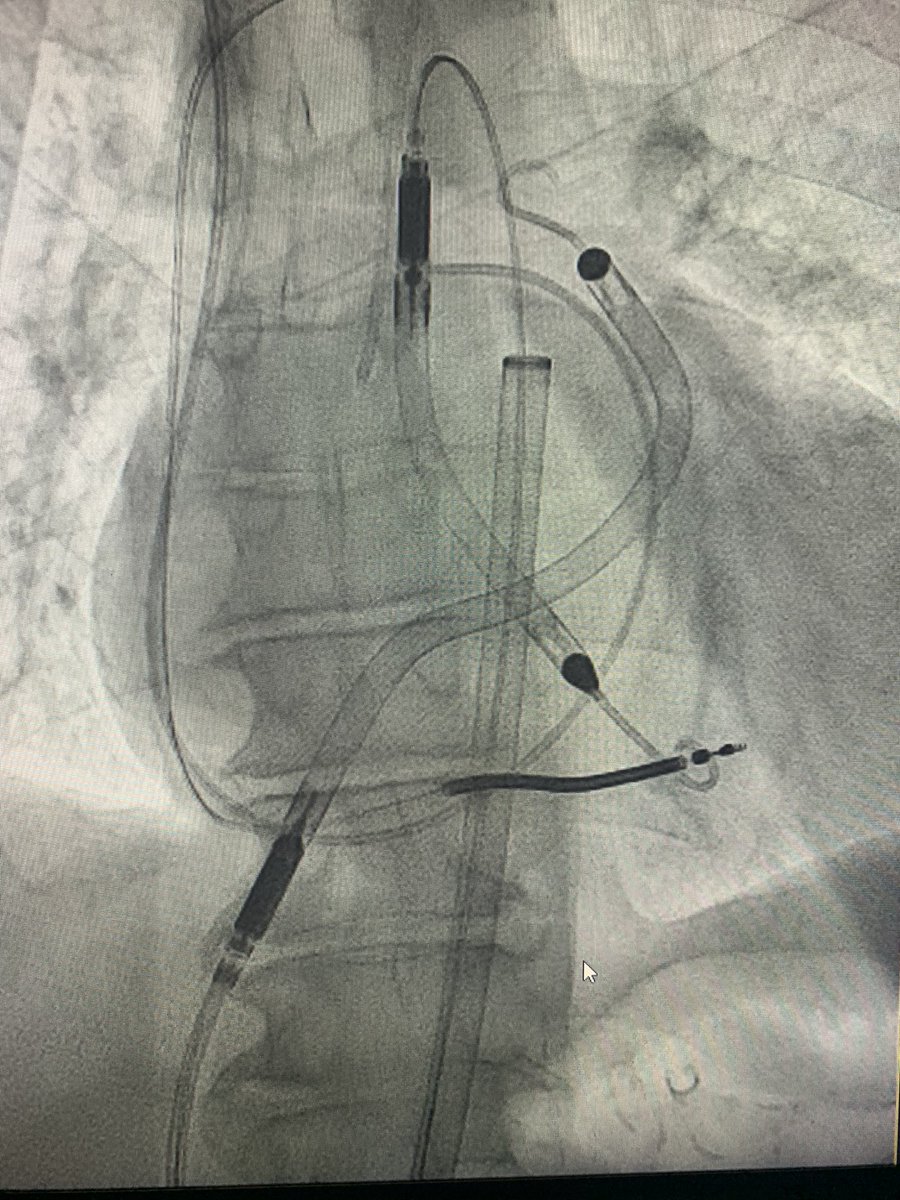

First transcaval TAVR in Baton Rouge. #transcaval #TAVR #Burn

jcastelltwitt's tweet image. First transcaval TAVR in Baton Rouge. #transcaval #TAVR #Burn

“Learning to Burn” w/ @JasonFoerst on my 1st #Transcaval access. Did #TAVR S3 23: 🚫PVL, mean AVG=2 by Cath, 6 by Echo; Final transcaval w/ minor Ao-C flow, type 1 closure. #CarilionStructural @CarilionSHD @Mjoseph3324 @SulaimanRathore @ShereeEmore @carmenhsalmon

Rahul2282Sharma's tweet image. “Learning to Burn” w/ @JasonFoerst on my 1st #Transcaval access.  Did #TAVR S3 23: 🚫PVL, mean AVG=2 by Cath, 6 by Echo; Final transcaval w/ minor Ao-C flow, type 1 closure.  #CarilionStructural @CarilionSHD @Mjoseph3324 @SulaimanRathore @ShereeEmore @carmenhsalmon